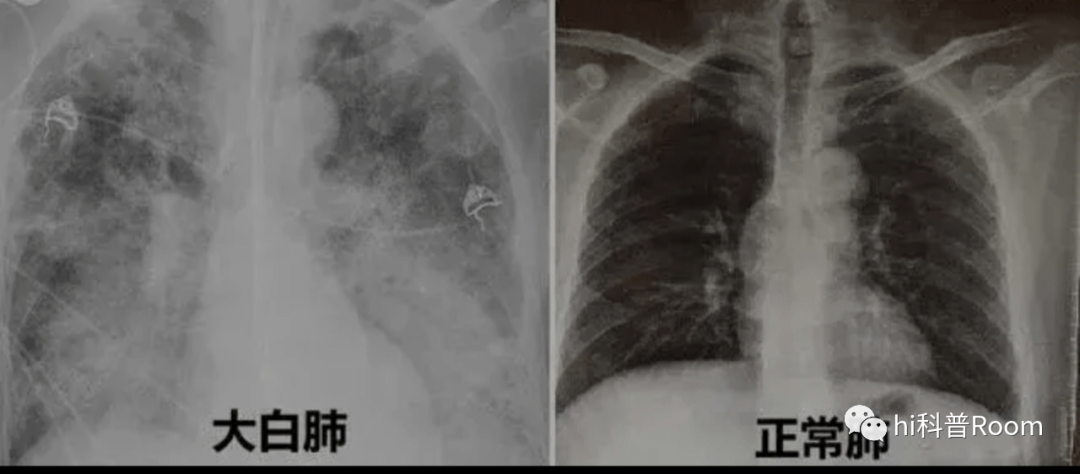

白肺的学名称之为急性呼吸窘迫综合征,肺里的肺泡大部分都是空气,因此正常人的肺在拍摄CT时,呈现出来的都是一片黑色。但如果肺里感染了炎症,射线就会被炎症细胞阻挡,拍摄出来的CT就是白色,一般白色区域超过70%就被称之为白肺。